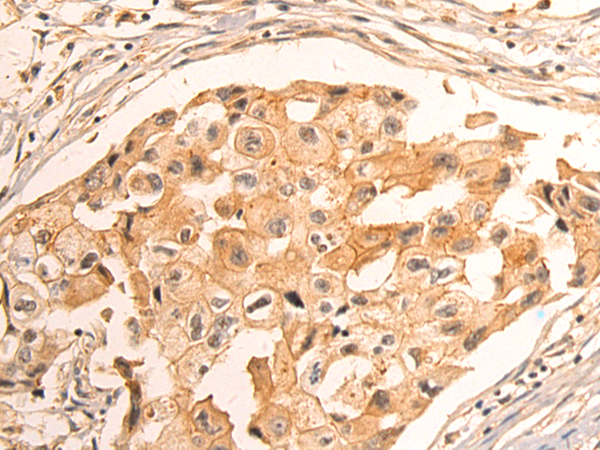

分类: 科研抗体货号: P12418别名: T1A; GP36; GP40; Gp38; OTS8; T1A2; TI1A; T1A-2; AGGRUS; HT1A-1; PA2.26应用: WB,IHC反应种属: Human